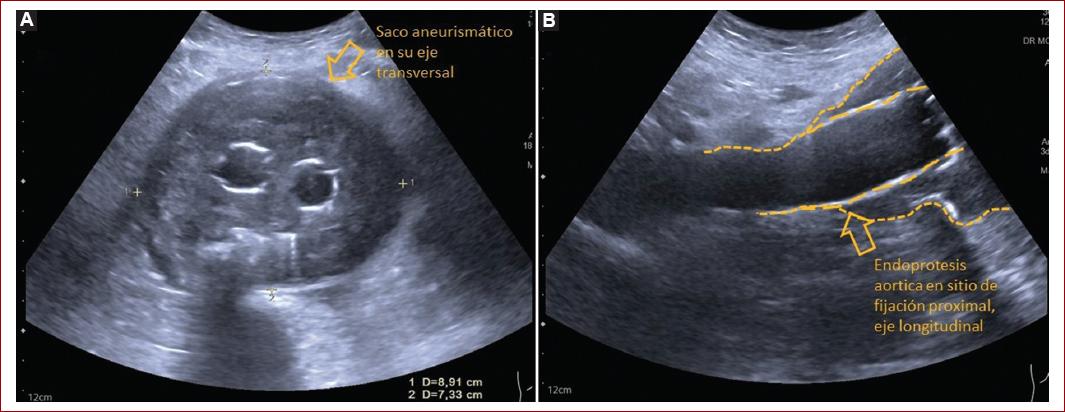

Análisis en modo B y escala de grises

- Se evalúa la aorta abdominal, arterias renales, tronco celíaco, arteria mesentérica superior, arteria mesentérica inferior y arterias ilíacas.

- Evaluar y documentar la posición de los sitios de anclaje proximal, distal.

- Evaluación del saco aneurismático en el eje axial y sagital, así como la medición del diámetro máximo del saco. La medición del eje axial se deberá realizar en relación con el eje del aneurisma y no con el eje del cuerpo del paciente (Fig. 3).